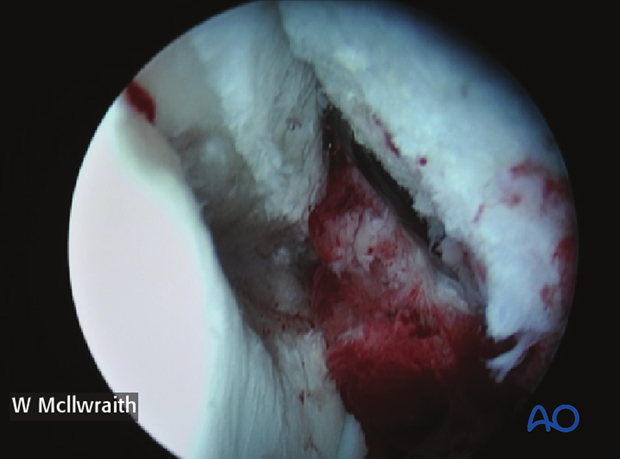

The dorsal compartment of the middle carpal joint should then be evaluated completely and any additional lesions noted. These fractures usually have significant displacement with a large fracture gap seen during arthroscopy.

This picture shows the defect after debridement and reduction by flexion.